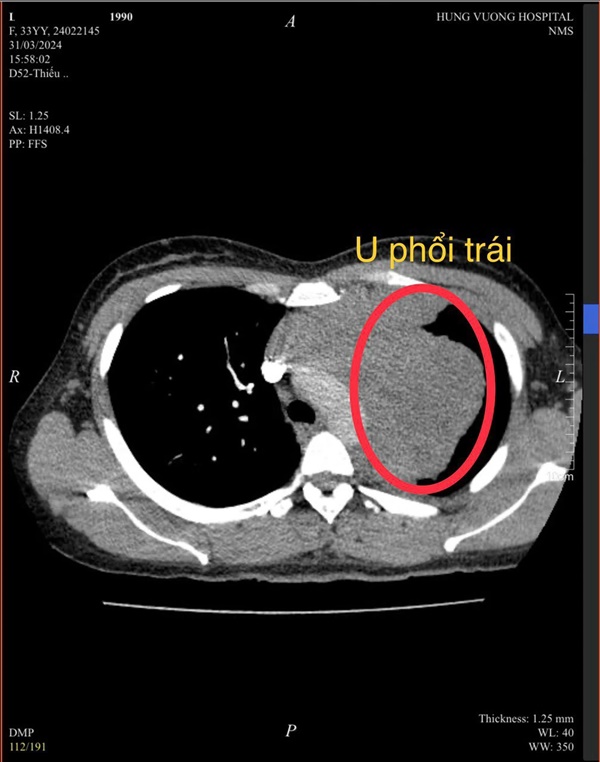

Tại đây, chị Hà được khám và tư vấn chụp cắt lớp vi tính phổi. Kết quả trên hình ảnh phim phát hiện khối u thuỳ trên phổi trái rất to, kích thước 9x12 cm. Các bác sĩ đã tiến hành sinh thiết, kết quả trả về kết luận: ung thư phổi (u ác) giai đoạn 3b.

Khối u phổi lớn bên thủy phổi trái (ảnh bác sĩ cung cấp).